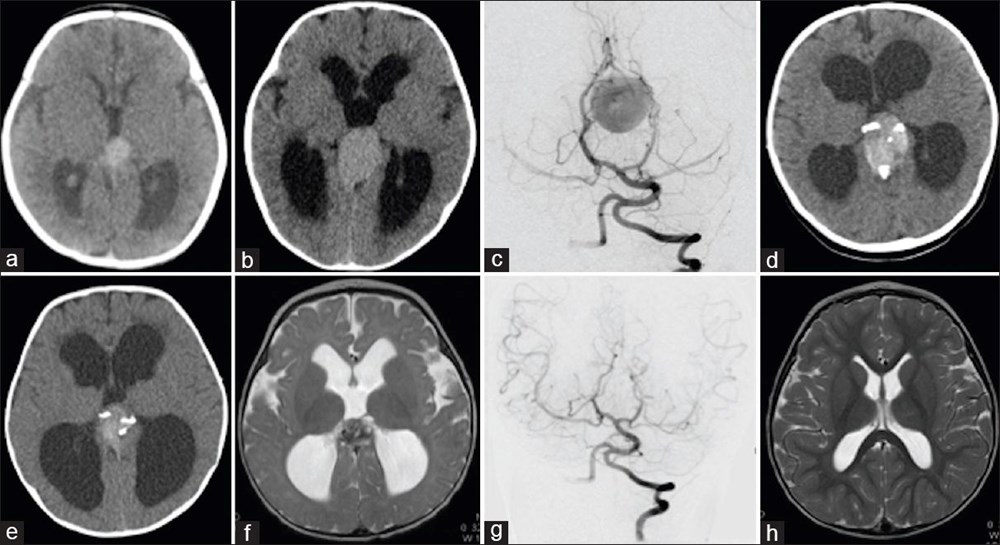

Genetik bir bozukluk olan Galen damarı Malformasyonu'ndan (VOGM) muzdarip rahimdeki bebeğin kafatasını kesmeyi ve ardından gelişmekte olan beyni ameliyat etmeyi içeren titiz bir prosedür gerçekleştiren doktorlar, dünyada ilk kez yapılan operasyon ile birçok çocuğun hayatının kurtarılabileceğini müjdeledi.Türünün ilk örneği olan ve hayat kurtaran bir prosedürle anne karnındaki bir bebeğe beyin ameliyatı yapıldı.ABD'li doktorlar doğmamış çocuktaki ölümcül bir damar rahatsızlığını tedavi ederek doğumdan kısa bir süre sonra kalp yetmezliği ve felç geçirmesini önledi. Daha önce de rahimde beyin ameliyatı yapılmıştı, ancak Galen Damarı Malformasyonu (VOGM) adı verilen bu nadir hastalık için yapılmamıştı.Anneyi 34. haftada ameliyat eden bilim insanları, operasyonu yönlendirmek için ultrason kullandı. BEBEK SAĞLIKLI BİR ŞEKİLDE EVİNE DÖNDÜBoston Çocuk Hastanesi'nden Dr. Darren Orbach konuyla ilgili yaptığı açıklamada, "Genellikle doğumdan sonra görülen bebeğin sağlığındaki düşüşün ortaya çıkmadığını görmek bizi çok heyecanlandırdı. Şu anda altı haftalık olan bebeğin, ilaç kullanmadan, normal beslenerek ve kilo alarak eve döndüğünü bildirmekten memnuniyet duyuyoruz. Operasyonun beyin üzerinde herhangi bir olumsuz etki belirtisi yok." dedi. GALEN DAMAR FORMASYONU HAKKINDABununla birlikte, Galen Damar Malformasyonu (VOGM) her yıl yüzlerce bebeği etkiliyor ve çocuklar doğumun ilk birkaç gününden sonra hayatta kalamayabiliyor. Hastalık, beyindeki atardamarların kanı kılcal damarlar yerine doğrudan toplardamarlara akıtmasına neden olarak kalbin boğulmasına ve beyin hasarına yol açıyor.Mevcut tedaviler ise şimdiye kadar bebeğin doğumundan sonrası ile sınırlıydı, ancak bu noktada çoğu vakada beyin hasarı çoktan meydana gelmiş oluyordu. "Stroke" adlı bilimsel dergide sonuçları açıklanan yeni cerrahi operasyon, hastalığı bebeği etkilemeden önce iyileştirmeyi amaçlıyor.Diğer taraftan, operasyon kapsamında 10 sağlık görevlisinden oluşan bir ekip, annenin karnından uzun bir iğneyi bebeğin beyninin arterlerin etkilendiği kısmına yönlendirmek için ultrason kullandı. Doktorlar, daha sonra damarlara geri akışı engellemek için damar içine küçük bir madde enjekte etti.Dr. Orbach, "Bu yaklaşım, Galen Damarı Malformasyonu’nun tedavisinde büyük bir potansiyele sahip. Malformasyonu doğumdan önce onarıyoruz ve doğumdan sonra tersine çevirmeye çalışmak yerine kalp yetmezliğini ortaya çıkmadan önlüyoruz. Bu, bu bebekler arasında uzun vadeli beyin hasarı, sakatlık veya ölüm riskini önemli ölçüde azaltabilir." diye konuştu.